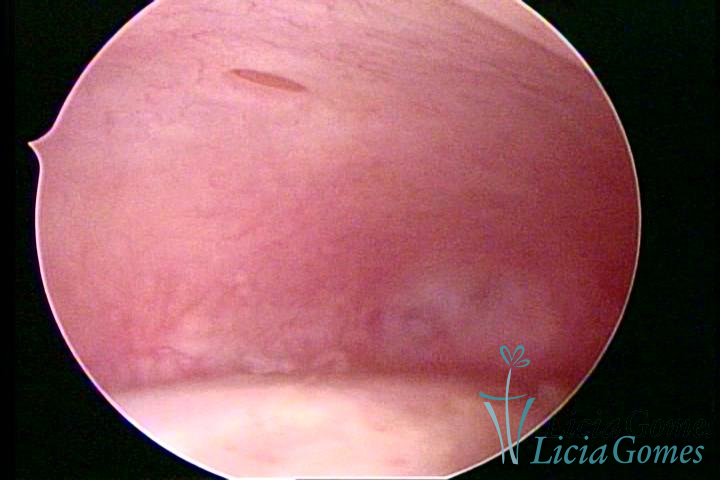

ADENOMYOSIS

The presence of endometrial tissue on the muscular layer of the uterus.

Video hysteroscopy allows diagnosing the lesions next to the superficial myometrial layers next to the endometrium, allowing the view of in situ, purplish, or chocolate brown lesions.